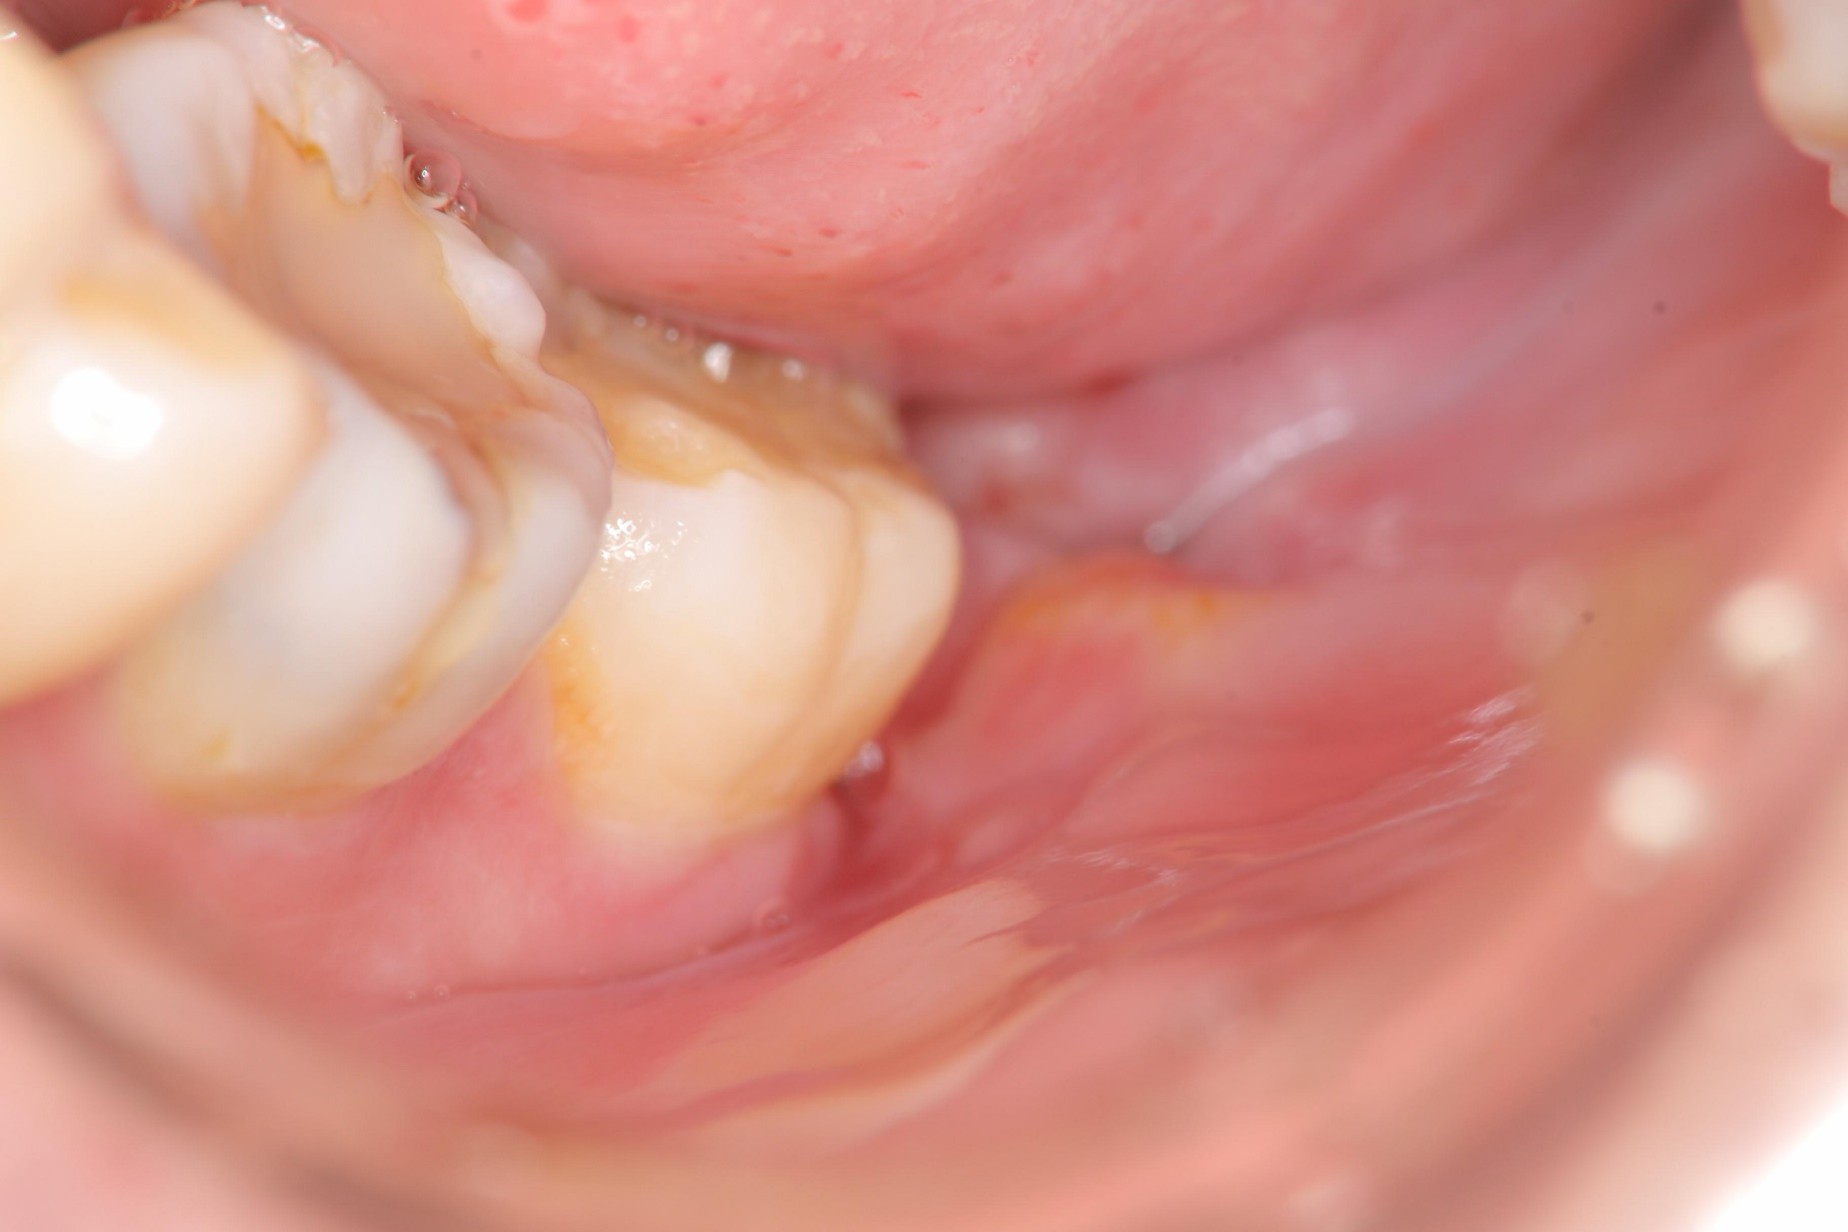

治療前

治療前,阻生齒牙齦經常腫脹